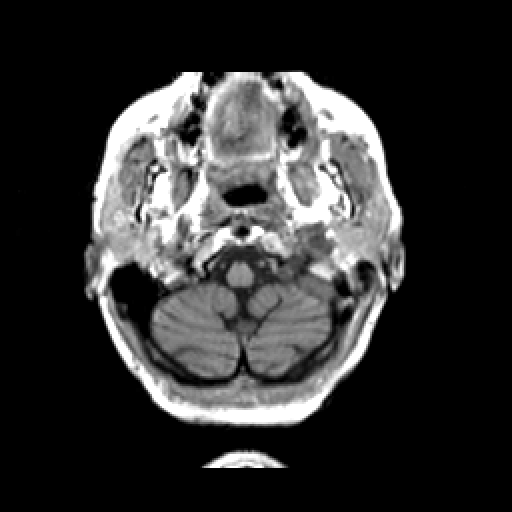

T1-weighted structural MR: Slice 6

Slice 6